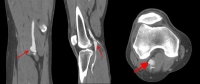

Management of popliteal artery aneurysms (PAA) aims to prevent major amputations caused by microemboli in the arteries of the lower leg from the aneurysm. In critical ischemia caused by PAA the rate of major amputation is between 25% and 50%.

Surgery is generally recommended for aneurysms measuring 2 cm in diameter and more, since even small aneurysms often become symptomatic. Since in aneurysms smaller than 2 cm with partial wall thrombosis and no pedal pulses "silent" embolization may be possible, the indication for surgery this situation must be determined on a case-by-case basis.

Acute and chronic critical ischemia, local pressure consequences, venous thrombosis due to compression, septic aneurysm and rupture constitute an indication for surgery regardless of the length or diameter.